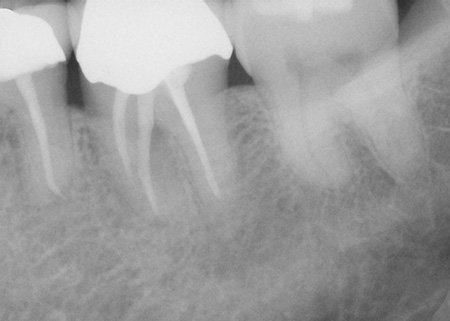

Vertical root fracture

As its name suggests, a vertical root fracture starts in the root and moves up toward the tooth surface. Because this crack isn’t visible right away, it may go undetected for a long time. Vertical root fractures are often the result of an infection of the gum or underlying jawbone. The tooth may need to be extracted to prevent further destruction of the surrounding tissues and bone.